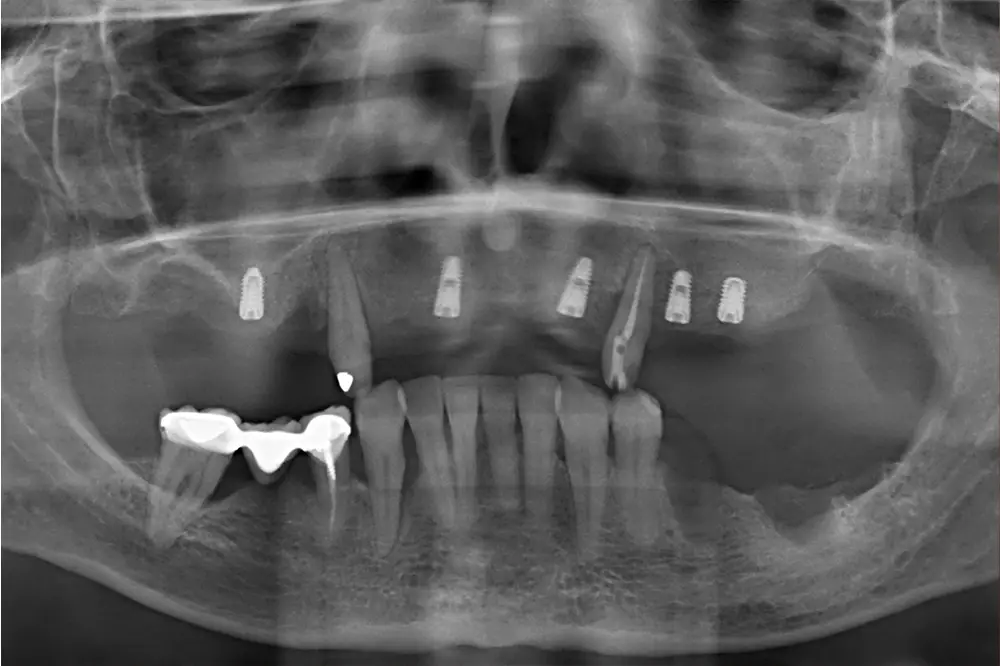

Al retirar las prótesis en las imágenes laterales, observamos además un colapso de la zona anterior y recesiones en todas las piezas que aún conserva la paciente (figs. 5 y 6). En la radiografía inicial observamos pérdidas óseas elevadas en el molar del primer cuadrante y el premolar de este mismo sector, por lo que se decide su exodoncia y regeneración con PRGF, que se realizará el mismo día de la primera fase de inserción de los implantes. En el arco inferior hay también problemas con los sectores posteriores, con pérdidas óseas en el cuarto cuadrante y signos de fractura vertical en el puente 44-46 y caries radicular en las piezas 35 y 36 (fig. 7). Por ello, estas piezas inferiores son también candidatas a la exodoncia, regeneración y reposición con implantes dentales, para lograr una posterior rehabilitación funcional.

Fig. 7. Radiografía panorámica inicial del caso, donde observamos la pérdida ósea del molar remanente del primer cuadrante y el primer premolar, que deciden extraerse y regenerarse la zona con PRGF-Endoret en el momento de la cirugía de implantes. Así mismo, las piezas 35 y 36 son también candidatas a la exodoncia por fracaso del tratamiento restaurador previo.